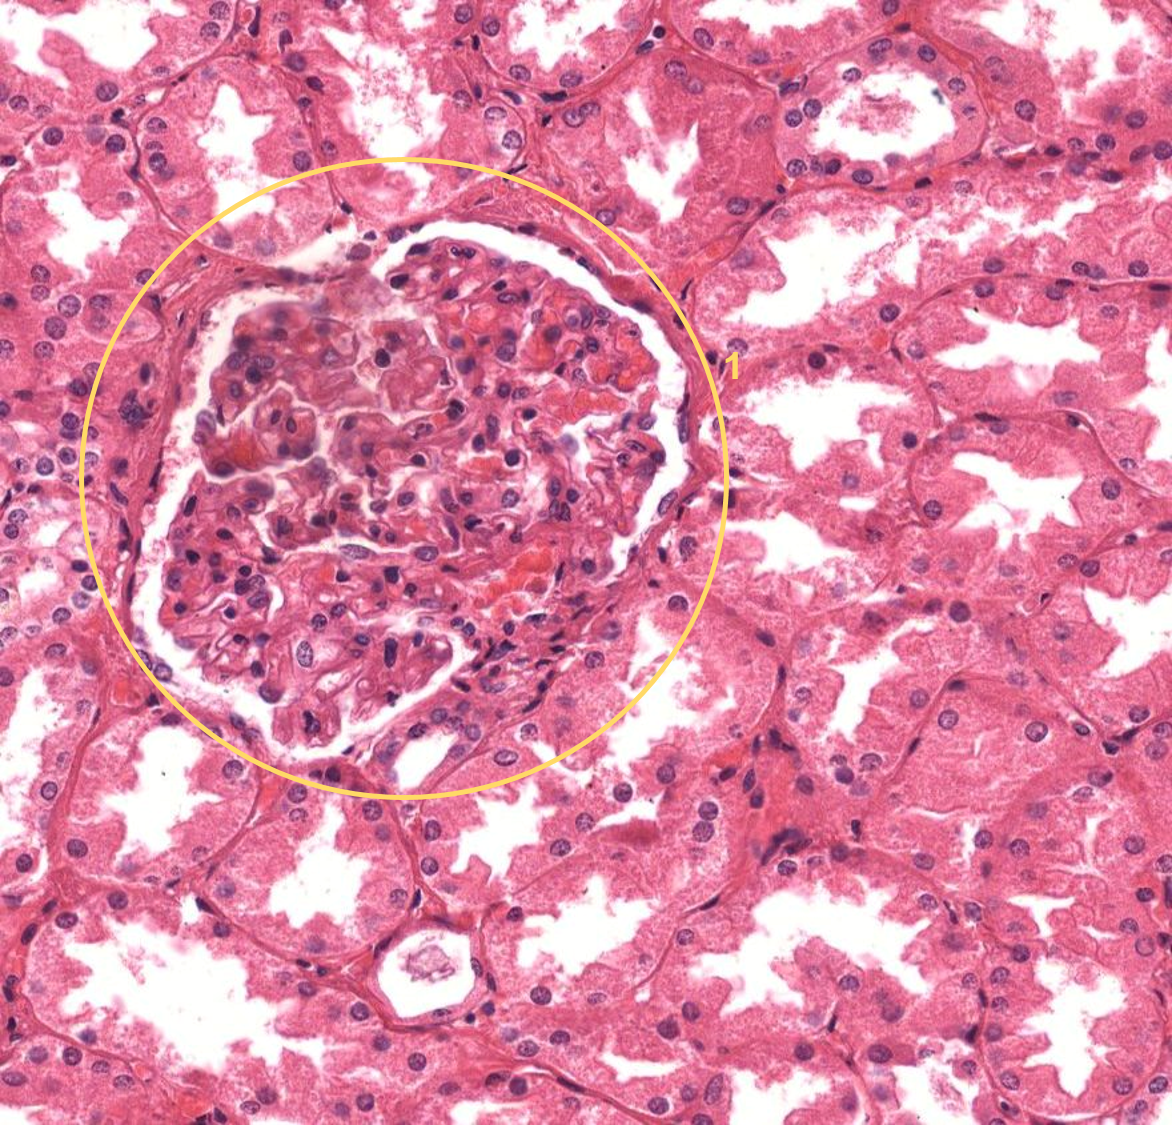

Rim - corpúsculo renal

Córtex renal

Córtex renal

1: Corpúsculo renal

2: Cápsula

Córtex renal